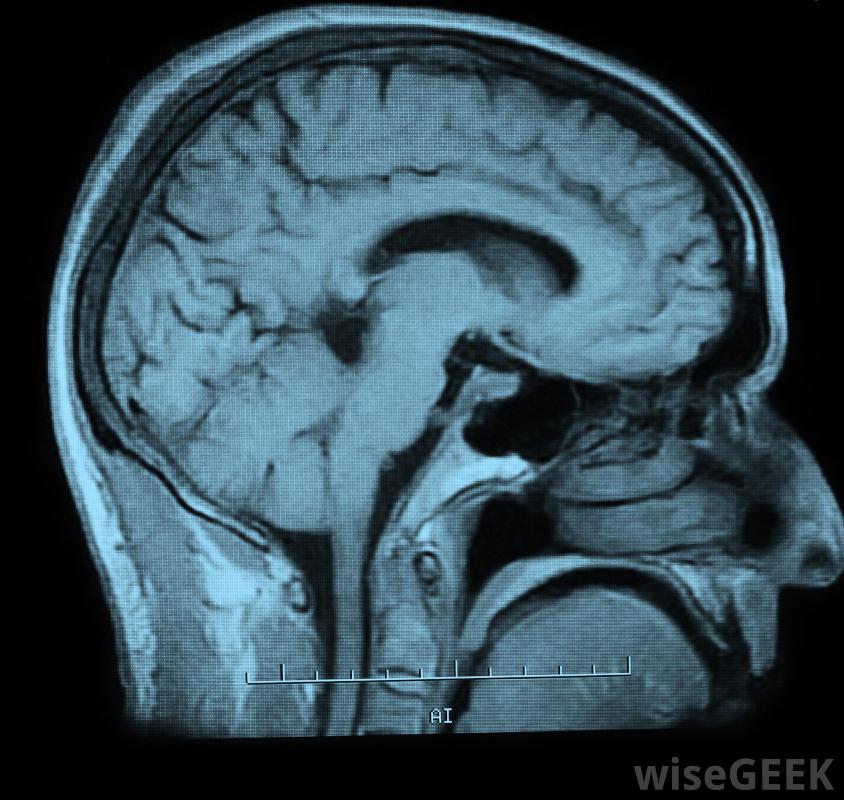

腰椎穿刺会清除一些保护脊髓的脑脊液一般情况下,这种类型的医疗程序不需要很好的准备。服用常规药物的人可能会被建议在进行腰椎穿刺之前停止某些处方的治疗。一些医生可能会在这个过程之前进行计算机断层扫描或磁共振检查核磁共振成像(MRI)。这些检查可以对大脑或脊柱进行全面检查。一般来说,医生会在手术前让患者知道他或她是否需要做任何特别的事情。病人需要住院治疗在背部穿刺时,通常会在背部注射消毒剂,用于麻醉,将针头插入腰椎,收集脑脊液。有些病人可能会被要求以某种方式定位,以便于液体的提取。医生通常建议病人躺下服用手术后容易。特别是剧烈的活动需要避免一整天腰椎穿刺术后最大的主诉通常是背部疼痛或头痛。对于这两种情况,建议服用止痛药。虽然如果疼痛加剧并出现其他并发症,则应联系医生